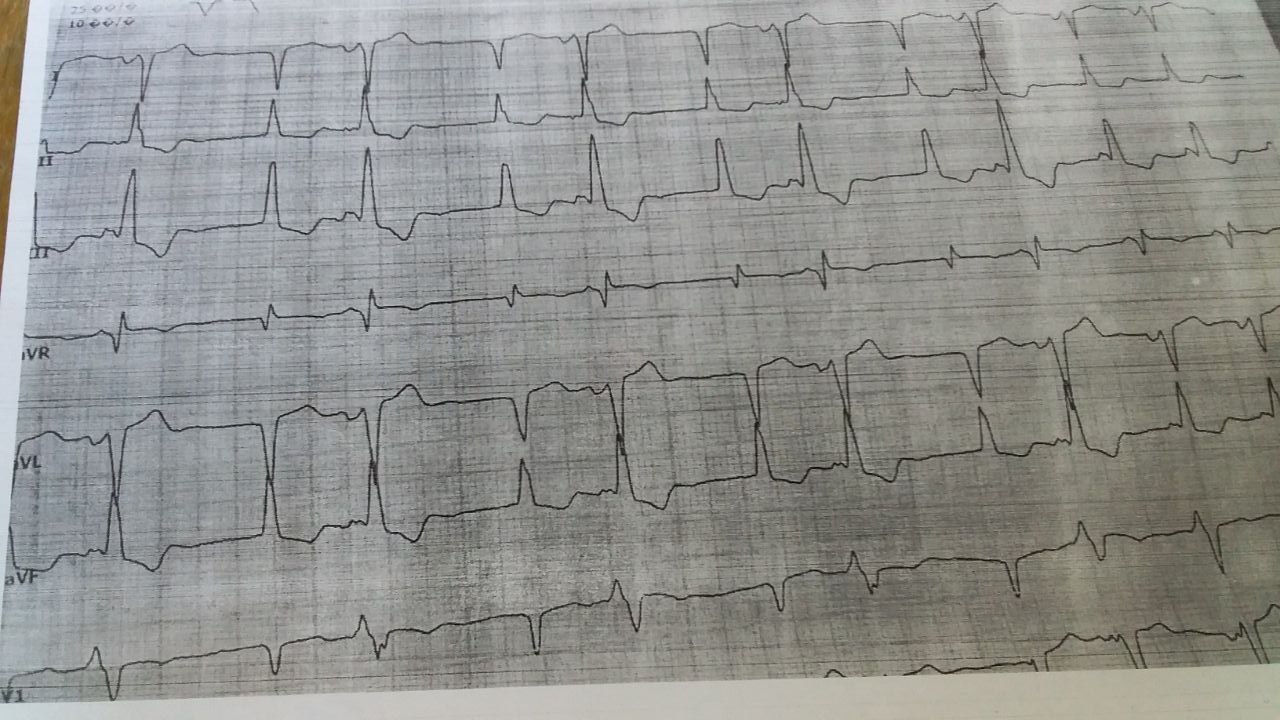

Ecg electrocardiography / ЭКГ электрокардиография

в комментариях написали верно - ан ЭКГ признаки гиперкалиемии: вероятно ритм из АВ-узла и высокие и заостренные зубцы Т

С чатика ХПН 5, на гемодиализа, Ад упало, гемодиализ пропустил, пил вино